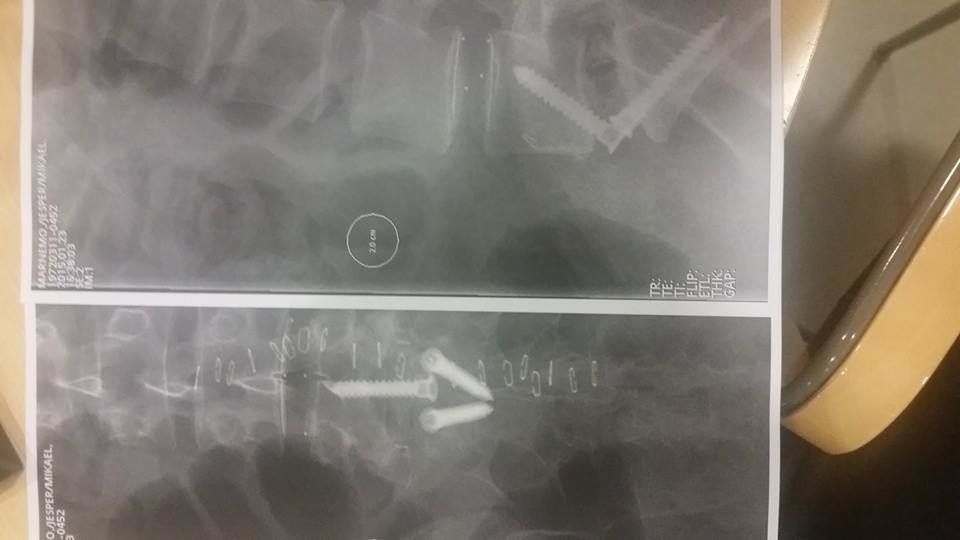

Fick min dom i veckan. Tre diskbuktningar som klämmer på tre olika nerver. L5-S1,L4 samt L3.